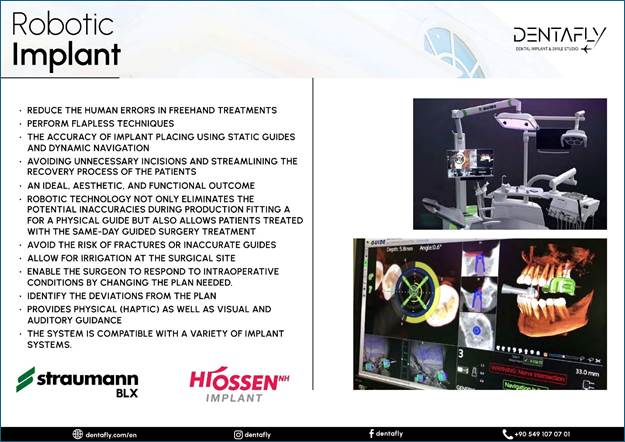

To AI Edge Ok I went to turkey to Antalya

to a company called Dentafly but before I left I sent picture through what’s

app of my teeth and received a quote of 1325 pounds the invoice stated I will

receive STRAUMMAN NEODENT IMPLANTS N ABUTMENTS

2 IMPLANTs but when I got there I see their head dentist and he

advise me to get better ones named Hiossen NH Hydrophilic Implants and one

extra crown which we never realized I needed. He quoted 375 for the extras.

The price of the crows is £125 pounds as in the invoice above, so he charged

an extra £250 pounds for the implant upgrades as I was told. I have got home now and

checked the first invoiced and it has a section with pictures and texted

titled as Dental Implants Which brands we are working with and

states Hiossen NH Hydrophilic Implants 490 pounds and Straumann BLX Implants

750 pounds. so, he charged me more and

give me rubbish ones by the pricing in their invoice. The image below is from the

invoice and proves the original Implant make!

The image provided below is

also from the first invoice and serves as evidence of the pricing listed in

their advertisements. It is important to note that there are six distinct

brands featured, accompanied by only three images. This potentially leads to

confusion, as each brand has its own unique pricing structure. Upon reviewing

their website, it becomes clear that these brands should each have their own

corresponding images; however, this is not the case. Furthermore, the layout is

compounded by the presence of only two divider lines, which implies that each

section contains multiple advertisements rather than a single advertisement

per brand. This setup undermines the clarity of the pricing information, as

it suggests a mix of prices for two different products within the same

section.

Evidence that these brands

should each have their own corresponding images, as they are their own brands,

is as below! https://dentafly.com/treatments/antalya-implant-treatment/

consultation with. Dt. Soner Arıkan Founder / MSc. Dentistry He graduated from the

Faculty of Dentistry at Gazi University in 2004. He has worked on

Aesthetic and Cosmetic Dentistry, Cad/Cam dental

treatments, and smile designs. He has been a certified dentist for brands

like Nobel Biocare Swedish Implant, Bego German Implant, I-System Screwless

Implant, and Straumann Swiss Implant since 2006. He wrote on a piece of paper the name of the recommended implant

upgrades and that is as follows: --